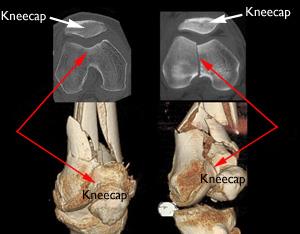

Οι ακτινογραφίες είναι η πιο κοινή και ευρέως διαθέσιμη διαγνωστική απεικονιστική τεχνική. Ακόμα κι αν χρειάζεστε και πιο εξελιγμένες εξετάσεις, πιθανότατα θα κάνετε πρώτα μια ακτινογραφία, καθώς οι ακτινογραφίες μπορούν να δείξουν ορισμένες ανωμαλίες καλύτερα από τις πιο εξελιγμένες εξετάσεις.

Τα οστά, οι ασβεστοποιήσεις, ορισμένοι όγκοι και άλλες πυκνές ουσίες εμφανίζονται λευκές ή ανοιχτόχρωμες επειδή απορροφούν την ακτινοβολία. Οι λιγότερο πυκνοί μαλακοί ιστοί και τα κατάγματα στα οστά αφήνουν την ακτινοβολία να περάσει, με αποτέλεσμα αυτά τα μέρη να φαίνονται πιο σκούρα στο ακτινογραφικό φιλμ.

Πιθανότατα θα σας κάνουν ακτινογραφία από διάφορες γωνίες. Εάν έχετε κάταγμα σε ένα άκρο, ο γιατρός σας μπορεί να θέλει μια συγκριτική ακτινογραφία του μη τραυματισμένου άκρου σας. Η συνεδρία ακτινογραφίας πιθανότατα θα ολοκληρωθεί σε περίπου 10 λεπτά. Οι εικόνες είναι έτοιμες γρήγορα. Είτε εμφανίζονται από το ακτινογραφικό φιλμ είτε αποστέλλονται ως ψηφιακά αρχεία για προβολή σε οθόνη υπολογιστή.